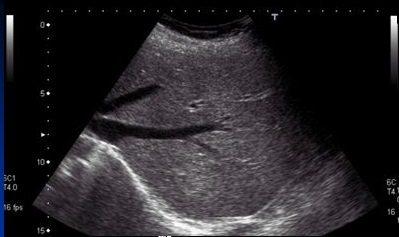

Image echographique de steatose du

foie est image du foie de plus en plus hyperechogene

homogene . Si la steatose est

important les branches de la veine porte sont

moins de visible et les structures profonde du foie

deviennent difficile a visualise . --Diagnostic echographique

de steatose du foie se represence lorsque le paenchyme

hepatique est beaucoup plus hyperechogene que le rein droit

. Au stade agrave , hepatomegalie et dilatation de veine

splenique et splenomegalie peut se en voyaient . Image de

distortion vasculaire sur Doppler en couleur et

amortissement du flux sanguine de la veine porte . Technique

echoelastographie peut en differencier que le foie steatose

est plus dure que foie normale .

Image echographique d'une

steatose du foie . la parenchyme du foie est tres

hyperechogene Les vaisseaux du foie sont en

moindre visible |